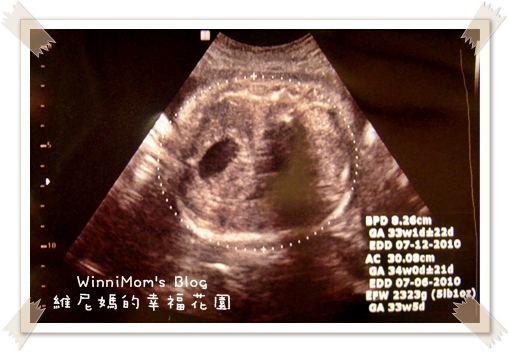

這次產檢,主要還是看看妮妹成長的速度與大小,這也是讓我比較worry的地方,

「為什麼她的頭圍總是小一個禮拜呢?」

妮妹的頭圍總是小一個禮拜.........................希望超音波有差距的說法,在妮妹身上會應驗。

妮妹還是有在長大,所以我不需要太過於擔心。

這上面的英文數字我也不太了解.....總之,我知道妮妹是健康的就好!